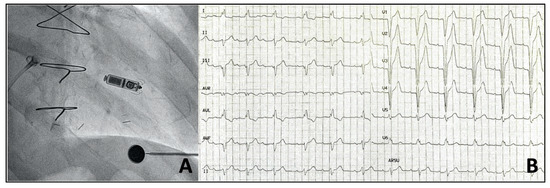

3. Conduction System Pacing

3.1. What Do We Already Know? Several Studies Have Shown the Feasibility, Safety, and Positive Clinical Outcomes of His Bundle Pacing (HBP) Compared with Customary RV Apical Pacing

3.2. Which Possible Indications for CSP?

- Burri, H.; Jastrzebski, M.; Vijayaraman, P. Electrocardiographic Analysis for His Bundle Pacing at Implantation and Follow-Up. JACC Clin. Electrophysiol. 2020, 6, 883–900. [Google Scholar] [CrossRef]

- Huang, W.; Su, L.; Wu, S.; Xu, L.; Xiao, F.; Zhou, X.; Ellenbogen, K.A. A Novel Pacing Strategy with Low and Stable Output: Pacing the Left Bundle Branch Immediately Beyond the Conduction Block. Can. J. Cardiol. 2017, 33, 1736.e1–1736.e3. [Google Scholar] [CrossRef]

- Vijayaraman, P.; Subzposh, F.A.; Naperkowski, A.; Panikkath, R.; John, K.; Mascarenhas, V.; Bauch, T.D.; Huang, W. Prospective evaluation of feasibility and electrophysiologic and echocardiographic characteristics of left bundle branch area pacing. Heart Rhythm 2019, 16, 1774–1782. [Google Scholar] [CrossRef]

- Huang, W.; Wu, S.; Vijayaraman, P.; Su, L.; Chen, X.; Cai, B.; Zou, J.; Lan, R.; Fu, G.; Mao, G.; et al. Cardiac Resynchronization Therapy in Patients with Nonischemic Cardiomyopathy Using Left Bundle Branch Pacing. JACC Clin. Electrophysiol. 2020, 6, 849–858. [Google Scholar] [CrossRef]

- Vijayaraman, P.; Chung, M.K.; Dandamudi, G.; Upadhyay, G.A.; Krishnan, K.; Crossley, G.; Campbell, K.B.; Lee, B.K.; Refaat, M.M.; Saksena, S.; et al. His Bundle Pacing. J. Am. Coll. Cardiol. 2018, 72, 927–947. [Google Scholar] [CrossRef]